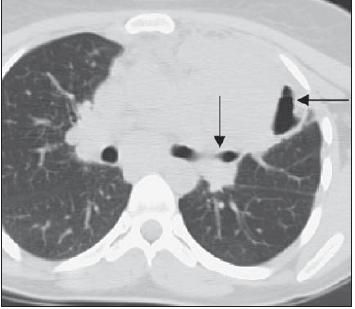

The patient's chest radiograph (Figure 1) and CT scan of the chest (Figure 2) are shown.

The patient's chest radiograph showed a large left suprahilar mass with cavitation (Figure 1). This was confirmed by a CT scan that showed a large area of consolidation, with an air bronchogram in the left upper lobe and an air-fluid level in the lateral part of the consolidation (Figure 2).

Figure 2 – This CT scan shows a large area of consolidation, with an air bronchogram in the left upper lobe (arrow) and an air-fluid level in the lateral part of the consolidation (arrow).